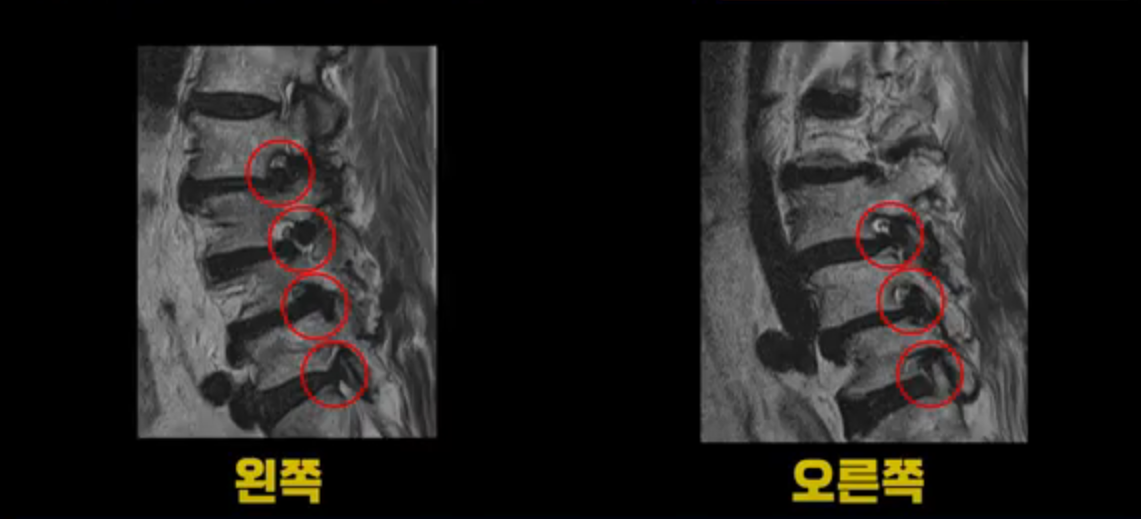

거의 모든 추간공 즉, 신경가지가 좌우로 빠져나가는 구멍이 다 좁아져 있습니다.